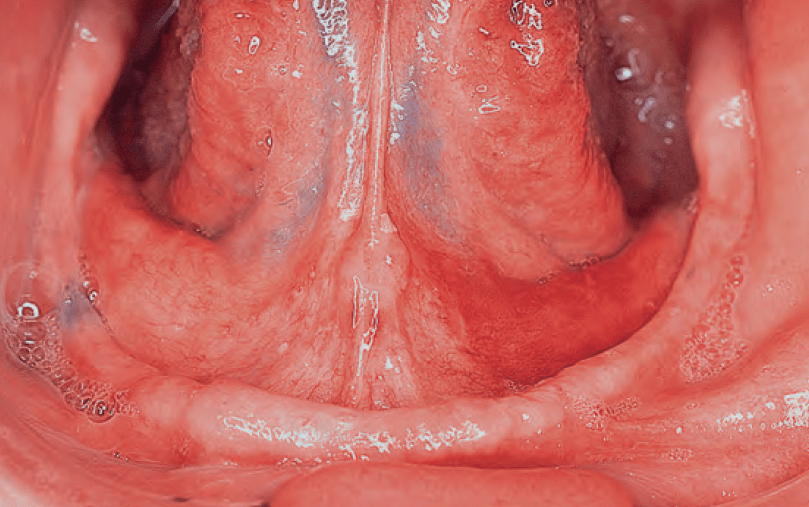

- Red spots, friable adjacent normal mucosa, characterize erythroplakia:

- It is associated with underlying epithelial dysplasia:

- Has a much greater potential for malignancy than leukoplakia:

- Carcinoma is found in nearly 30% to 40 % of cases of erythroplakia

- Erythroplakia usually manifests as a pinkish, velvety flat

- Speckled leukoplakia:

- Has a particularly high incidence of malignant transformation:

- Similar to erythroplakia